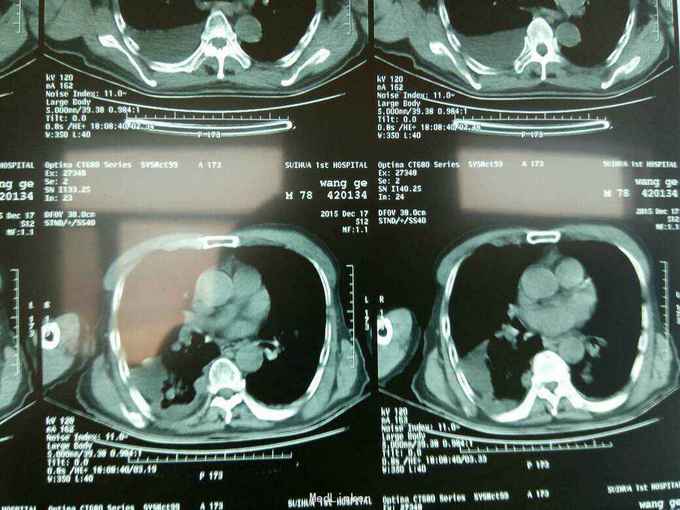

根据病史查体诊断:腰间盘突出症待确诊。应用消肿营养神经镇痛治疗。一天。查核磁共振示:腰椎多节段间盘突出伴椎管狭窄。第二腰椎骨破坏侵及椎板。部分突入椎管,脊髓受压。诊断:腰间盘突出伴椎管狭窄。第二腰椎转移癌,脊髓受压。经与家属沟通,查双肺CT:双肺下叶炎症。肺部纤维化。可见肿瘤阴影。肋骨及胸膜受累。胸椎部分骨破坏。最终诊断:双肺癌,胸椎,腰椎骨转移,脊髓受压。多节段腰椎间盘突出。病人至肿瘤科治疗。